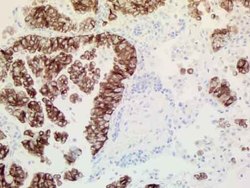

- Invitrogen Antibodies (provider)

- Main image

- Experimental details

- Immunohistochemical staining of paraffin-embedded human ALK-positive lung cancer tissue using anti-ALK mouse monoclonal antibody. (TA801287, 1:100 for 30 min at RT; heat-induced epitope retrieval by TEE, pH9.0)